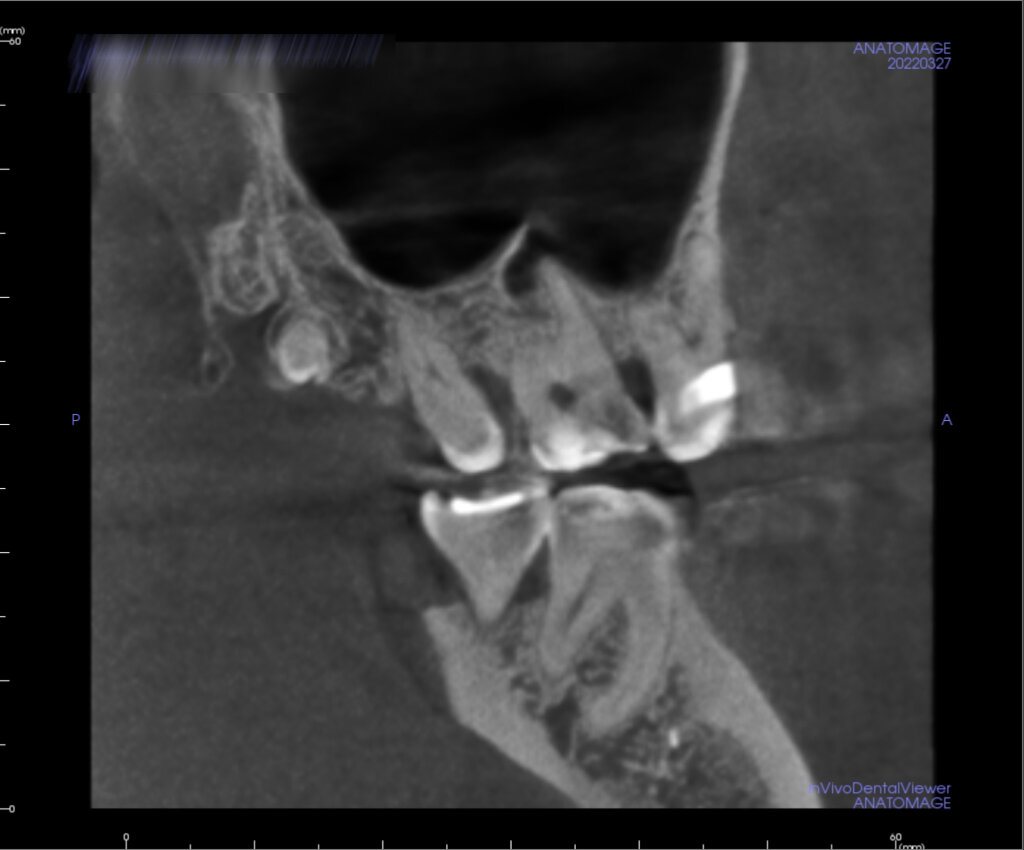

На диагностическом снимке сверхкомплектный 9й зуб

Определить непрорезавшиеся лишние зубы и изучить строение, расположение, форму, размеры можно посредством 3D-снимка, который можно сделать при помощи #компьютерной томографии. Также по результатам обследования лечащий врач может составить полную клиническую картину патологии и назначить дальнейшее лечение.